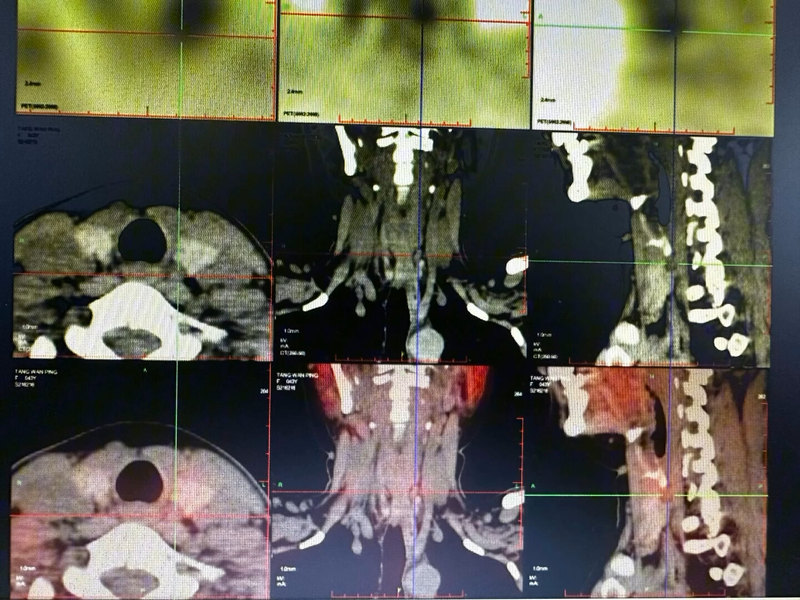

一、病例資料患者女,42歲。10年前診斷為“局灶節(jié)段性腎小球硬化癥(FSGS)”。8年前開(kāi)始行持續(xù)不臥床腹膜透析(CAPD)治療病情好轉(zhuǎn),能夠堅(jiān)持工作。3年前全身皮膚瘙癢,進(jìn)行性加重,雙腿不適,靜置不能,否認(rèn)骨及關(guān)節(jié)疼痛,查血鈣2.91mmol/L,血磷1.83mmol/L,ALP74IU/L,血iPTH648pg/ml,曾給予羅蓋全沖擊治療,癥狀及生化指標(biāo)無(wú)改善。1年半前查血鈣2.71mmol/L,血磷2.14mmol/L,ALP155U/L,血iPTH1268pg/ml,甲狀旁腺彩超示:甲狀腺左葉下極及后方見(jiàn)1個(gè)0.90.6cm的低回聲,右葉下極后方見(jiàn)2個(gè)低回聲1.30.9cm,1.20.6cm,邊界清晰,內(nèi)部回聲均勻,有包膜。其內(nèi)可探及較豐富血流信號(hào),符合甲狀旁腺增生。診斷“繼發(fā)性甲狀旁腺功能亢進(jìn),慢性腎衰竭尿毒癥期,腹膜透析,不安腿綜合癥”。于2009年5月20日在中日友好醫(yī)院行全麻下行甲狀旁腺全切除術(shù)+前臂移植術(shù)(PTx+AT),術(shù)中探查切除4枚甲狀旁腺,左上0.50.8cm,左下0.71.2cm,右上0.50.7cm,右下0.81.2cm(見(jiàn)圖12-4-1),肉眼觀察右上甲狀旁腺組織相對(duì)正常,取約30mg切碎后移植于右前臂肌肉中。術(shù)后病理證實(shí)切除的4枚組織全部為甲狀旁腺結(jié)節(jié)狀增生組織。術(shù)后當(dāng)日皮膚瘙癢及腿部不適完全緩解,術(shù)后一周監(jiān)測(cè)iPTH波動(dòng)于40~60pg/ml,補(bǔ)鈣治療達(dá)正常血鈣后出院。2010年10月患者因?yàn)榧着钥簭?fù)發(fā)再次復(fù)診,訴皮膚瘙癢及腿部不適6個(gè)月,癥狀同2009年術(shù)前,查血鈣3.14mmol/L,血磷1.81mmol/L,血iPTH波動(dòng)于600pg/ml,ALP正常,頸部甲狀旁腺彩超未發(fā)現(xiàn)增大甲狀旁腺,右前臂彩超未發(fā)現(xiàn)血流豐富的疑似甲狀旁腺移植物,分別抽血檢查右臂iPTH2620pg/ml,左臂664pg/ml,進(jìn)一步行MIBI+SPECT/CT核素?cái)鄬訏呙琛拔窗l(fā)現(xiàn)頸部或胸骨后異位甲狀旁腺,右前臂放射性濃聚灶,結(jié)合病史考慮種植甲狀旁腺功能增強(qiáng)”(見(jiàn)圖12-4-2),診斷“繼發(fā)性甲狀旁腺功能亢進(jìn)術(shù)后復(fù)發(fā)”。???二、治療過(guò)程患者希望再次手術(shù)切除移植物,2011年2月于我院行臂叢麻醉下行甲狀旁腺移植物取出術(shù),術(shù)中未發(fā)現(xiàn)前臂肌肉有異常組織樣包塊,按照SPECT/CT定位標(biāo)記切除約30g肌肉組織,術(shù)后病理回報(bào)“未見(jiàn)甲狀旁腺組織,切取組織為肌肉組織及部分脂肪組織”,術(shù)后皮癢、不安腿、失眠癥狀僅緩解3天后再度出現(xiàn),查血Ca3.36mmol/L,血P1.91mmol/L,前臂移植側(cè)驗(yàn)血iPTH800pg/ml。2012年再次局麻下切除前臂肌肉甲狀旁腺移植物,術(shù)后3個(gè)月再次復(fù)發(fā),患者服用西那卡塞約2年,SHPT控制不佳,堅(jiān)決要求再次手術(shù),于2014年行前臂多點(diǎn)肌肉無(wú)水酒精注射治療,術(shù)后成功控制血鈣、磷和PTH在達(dá)標(biāo)范圍,隨訪8年病情穩(wěn)定。三、討論這是我們團(tuán)隊(duì)治療唯一的一例PTX+AT術(shù)后復(fù)發(fā)、多次切除前臂甲狀旁腺移植物效果不佳的CAPD患者??紤]患者SHPT復(fù)發(fā)原因與術(shù)后鈣磷控制欠佳、透析不夠充分、西那卡塞等藥物治療不充分(當(dāng)時(shí)西那卡塞是自費(fèi)藥物),移植物甲狀旁腺細(xì)胞增值過(guò)于旺盛有關(guān)。通過(guò)檢查雙前臂iPTH差值和MIBI+SPECT/CT確診右前臂甲狀旁腺移植物SHPT復(fù)發(fā)?,F(xiàn)在也有越來(lái)越多的學(xué)者主張選擇甲狀旁腺全切除術(shù)并不移植的術(shù)式,尤其對(duì)于SHPT病變較重,發(fā)現(xiàn)切除的甲狀旁腺腺體都為明顯增大,類似于結(jié)節(jié)增生狀態(tài)時(shí),移植后復(fù)發(fā)風(fēng)險(xiǎn)增大。通過(guò)此例經(jīng)驗(yàn),以后我院開(kāi)展PTX+AT術(shù)式以皮下甲狀旁腺組織塊移植為主,術(shù)后1-6月多數(shù)患者移植物存活,僅個(gè)別病例有移植物亢進(jìn)需要手術(shù)取出的病例。(中日友好醫(yī)院提供病歷)此文出自科學(xué)出版社新書《慢性腎臟病甲狀旁腺功能亢進(jìn)》第十二章